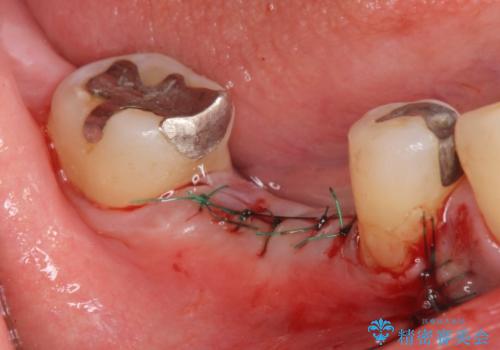

無事インプラントが入りました。

インプラント治療をしてもメンテナンスを怠っているとインプラント歯周炎になるリスクがあがるのでメンテナンスをお勧めします。